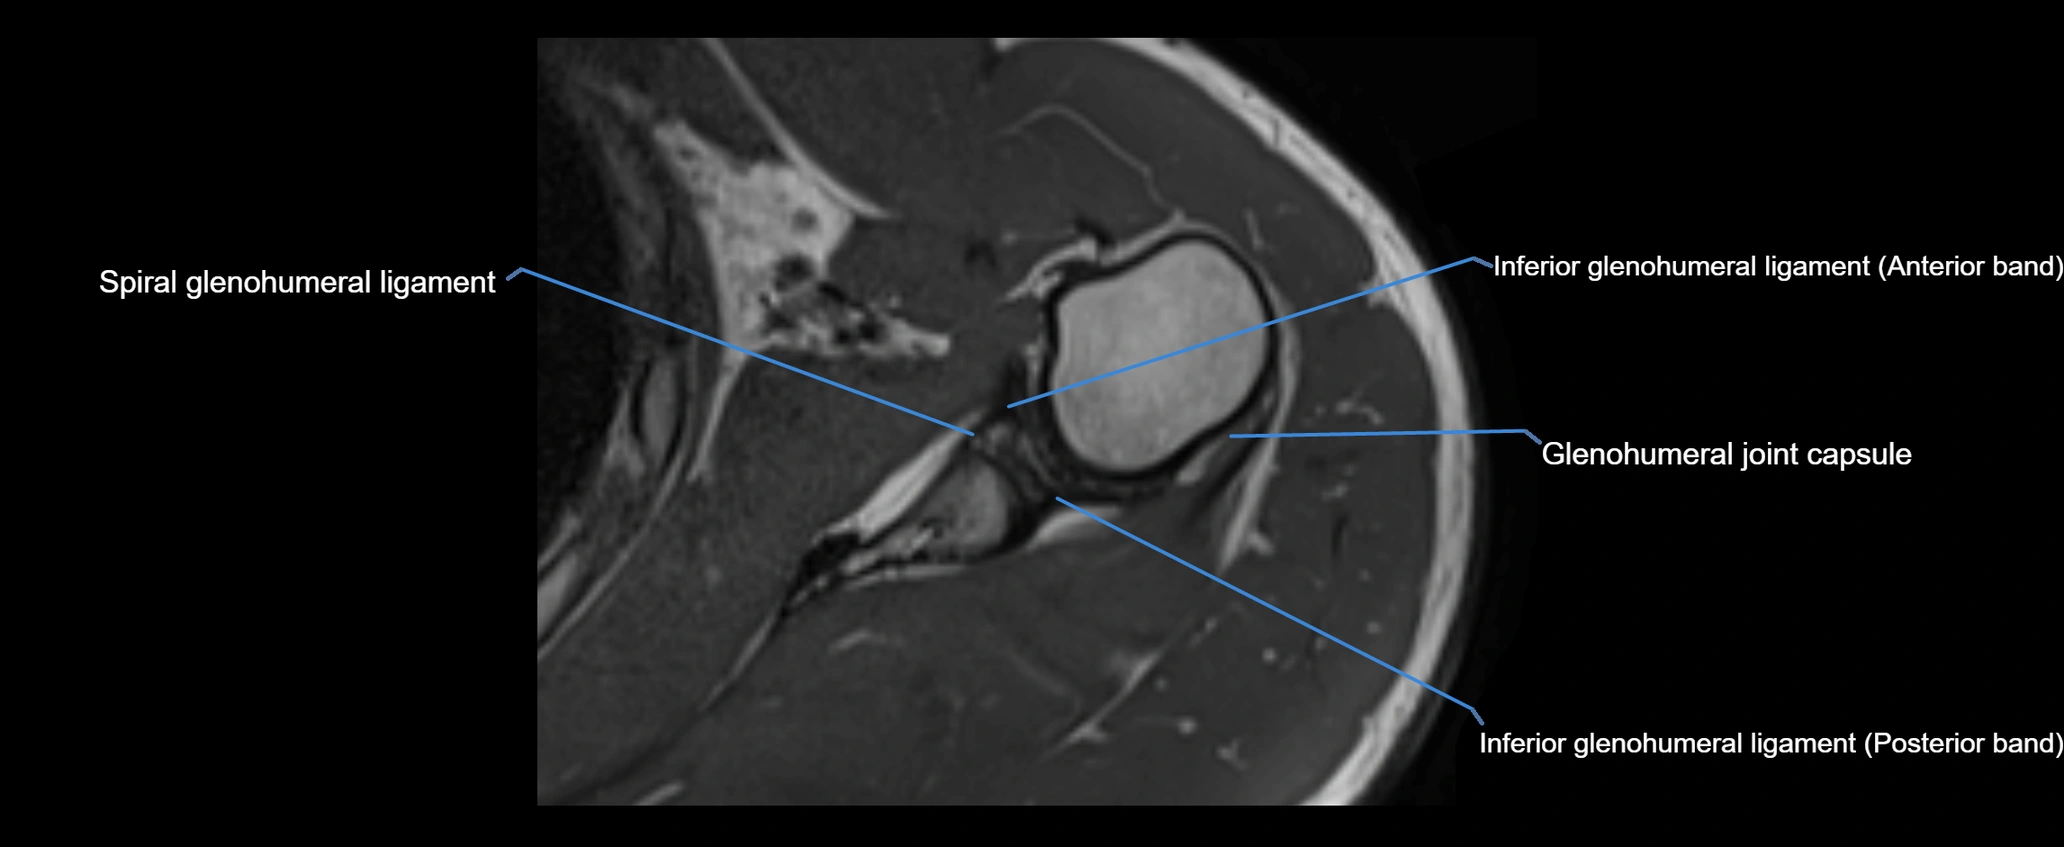

MRI images

image